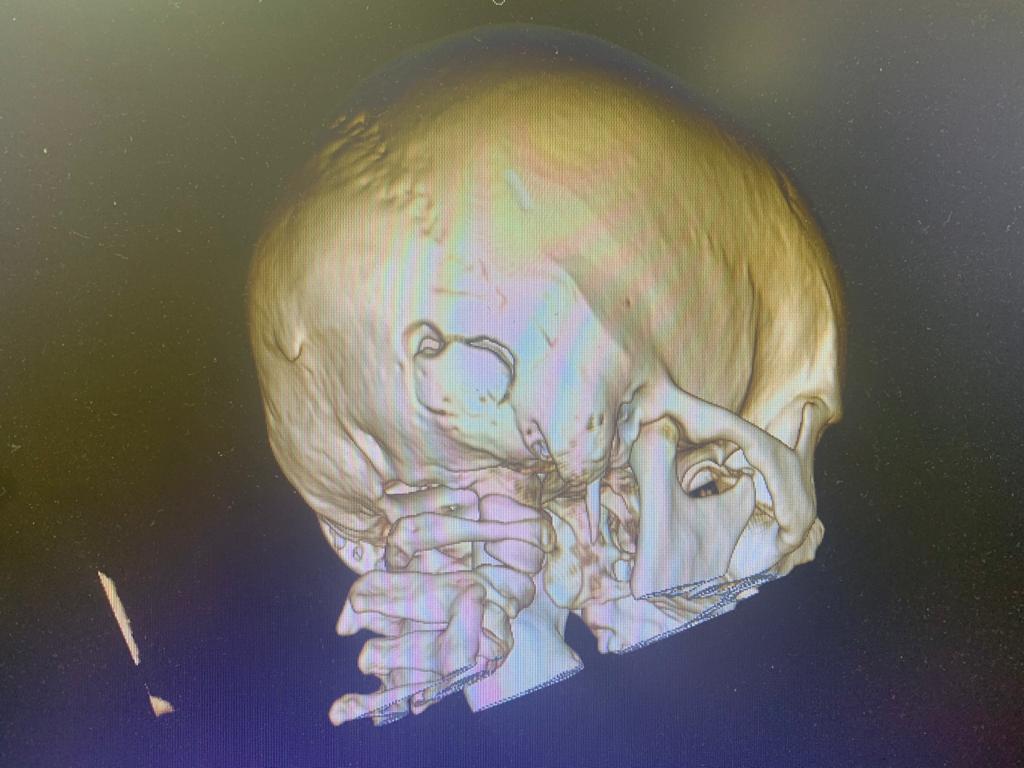

Были назначено полное обследование пациента. На МРТ головного мозга выявлена кавернома правого полушария мозжечка,  имелись признаки перенесённого кровоизлияния. Учитывая хирургическую доступность к каверноме, нейрохирурги клиники выполнили операцию, пациент при этом находился в положении сидя.

Кавернома удалена тотально.